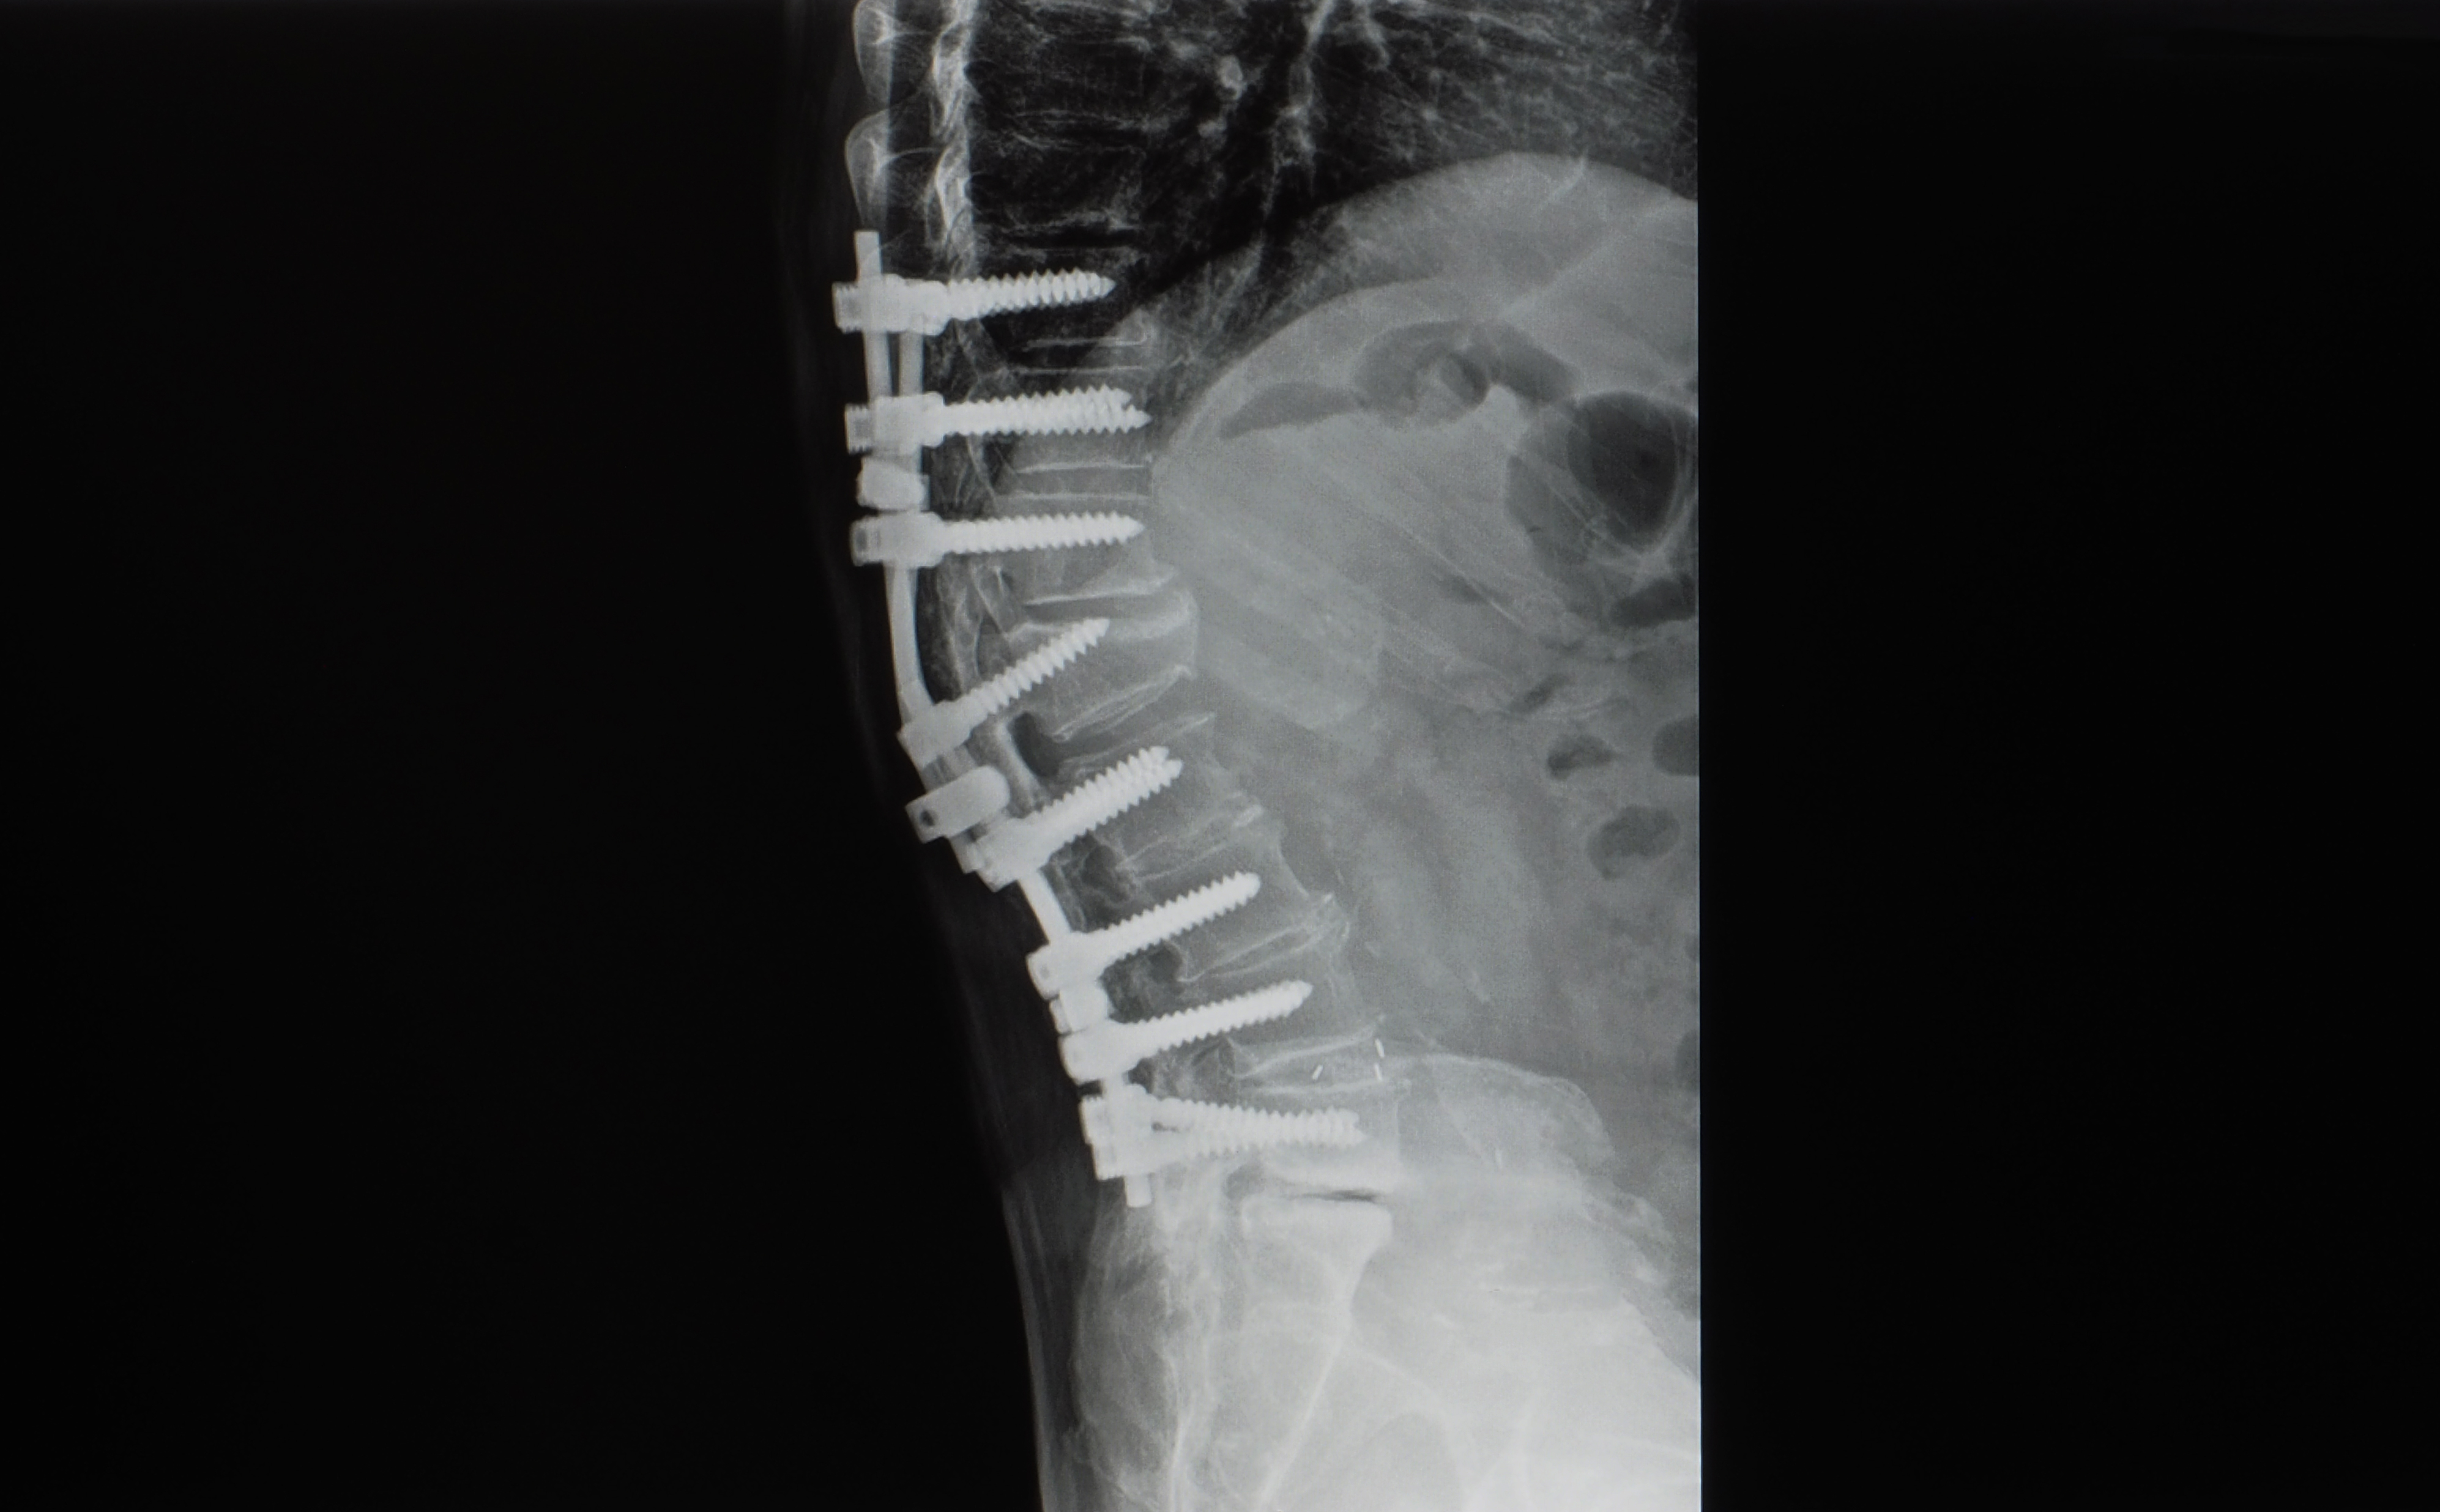

Normal Variants refer to skeletal conditions that are altered within the normal range, and Congenital Abnormality refers to congenital skeletal variations. Although there are variations that do not cause clinical problems, some types (especially congenital abnormalities) can be important factors in causing musculoskeletal pain, and some of them can be contraindications for manual therapy.

The most important thing to be careful about in manual therapy is contraindications. Therefore, this course is an essential subject that all manual therapy specialists must study without exception, as it can prevent side effects from manual therapy by identifying skeletal deformation through x-ray images, and it is a field that is strongly recommended as a prerequisite for manual therapy technique subjects.

The skeletal deformation of the musculoskeletal system can be accurately diagnosed through x-ray. Therefore, side effects that may occur during manual therapy can be prevented in advance, and the indications, contraindications, and target of manual therapy can be clearly recognized.